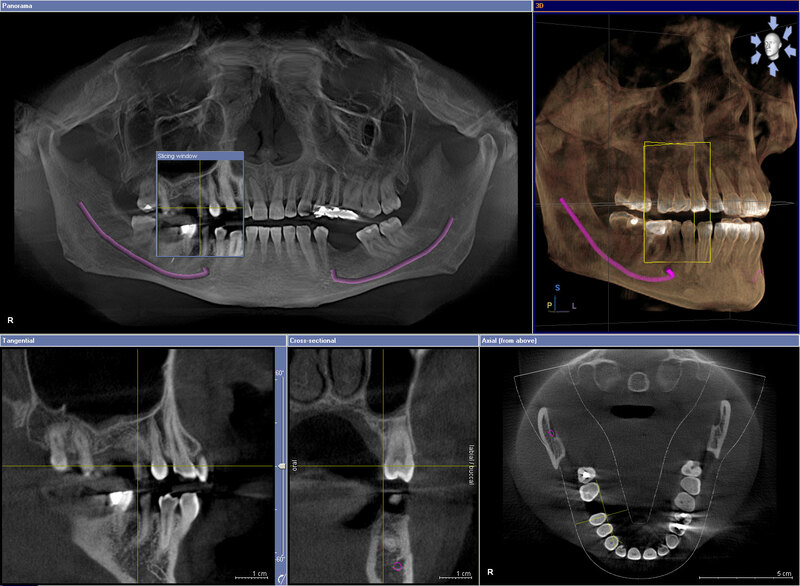

- Chụp CT hình nón (X quang 3 chiều): Đây là một tiến bộ công nghệ cho phép nha sĩ xem các cấu trúc không thể nhìn thấy bằng mắt thường. Chụp CT hình nón sử dụng thiết bị X quang quay kết hợp với máy vi tính kỹ thuật số để tạo ra hình ảnh 3 chiều của mô mềm, cơ xương hàm, mạch máu và thậm chí là ống dây thần kinh.